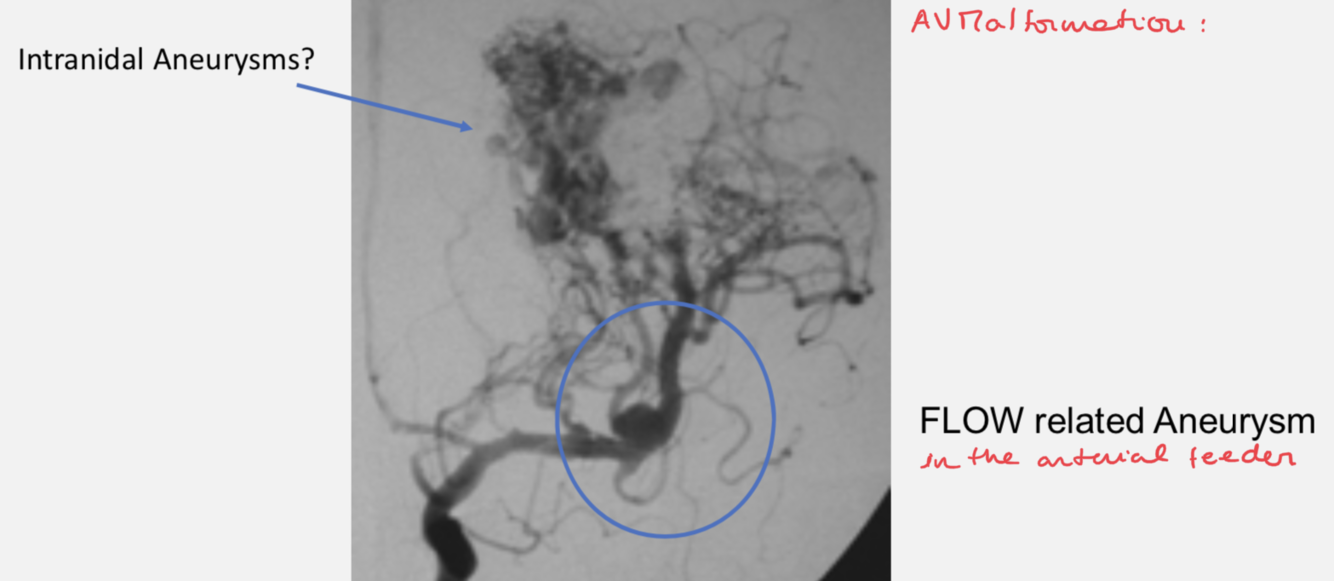

AVM - architecture

AVM - nidus:

AVM - topography and vessels involved